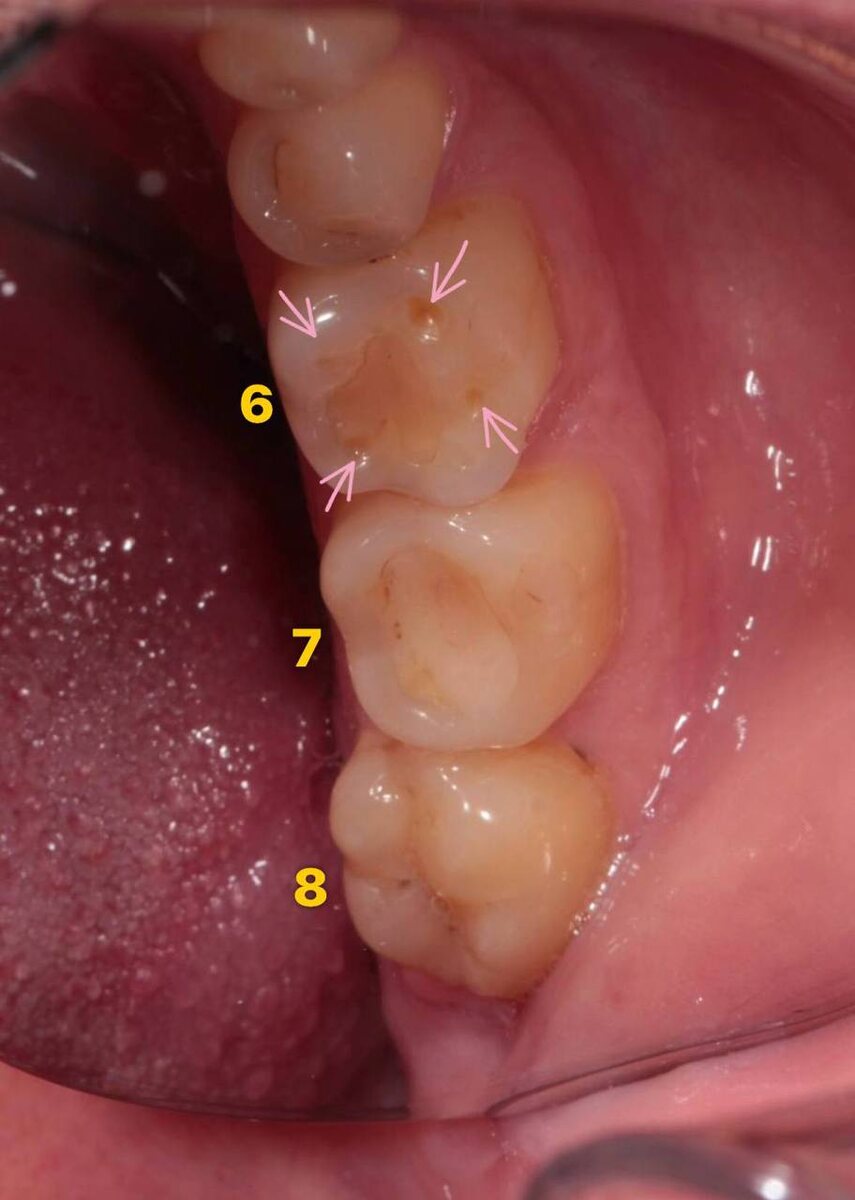

⚡️ Давайте сегодня про то, что вы можете увидеть у себя, рассмотреть и применить к своим зубам. Помечены зубы 6️⃣, 7️⃣и 8️⃣. Это моляры, жевательные зубы. Если вы посмотрите на 8️⃣, тот, который зуб мудрости, то, как ни странно, именно таким образом плюс-минус должен выглядеть зуб: ➖ четкие, хорошо выраженные бугры ➖ фиссуры - естественные углубления, бороздки. Про них отдельно нужно будет написать! 🙏 Не позыбыть бы!!! Вы наверняка заметили, что 6️⃣ и 7️⃣ отличаются от этого зуба: 🔜 наличие пломб на жевательных поверхностях 🔜 пломбы «просели», имеется зазор между ними и поверхностью зуба 🔜 бугры не столь очерчены, как на их соседе 🔜 на 6-м имеются какие-то ямочки (обозначила стрелочками) Это пока то, что мы видим глазами. Есть? Чуть позже - небольшие пояснения 💻 #стоматолог #Москва

Помечены зубы 6️⃣, 7️⃣и 8️⃣. Это моляры, жевательные зубы.

Если вы посмотрите на 8️⃣, тот, который зуб мудрости, то, как ни странно, именно таким образом плюс-минус должен выглядеть зуб:

➖ четкие, хорошо выраженные бугры

➖ фиссуры - естественные углубления, бороздки. Про них отдельно нужно будет написать! 🙏 Не позыбыть бы!!!

Вы наверняка заметили, что 6️⃣ и 7️⃣ отличаются от этого зуба:

🔜 наличие пломб на жевательных поверхностях

🔜 пломбы «просели», имеется зазор между ними и поверхностью зуба

🔜 бугры не столь очерчены, как на их соседе

🔜 на 6-м имеются какие-то ямочки (обозначила стрелочками)